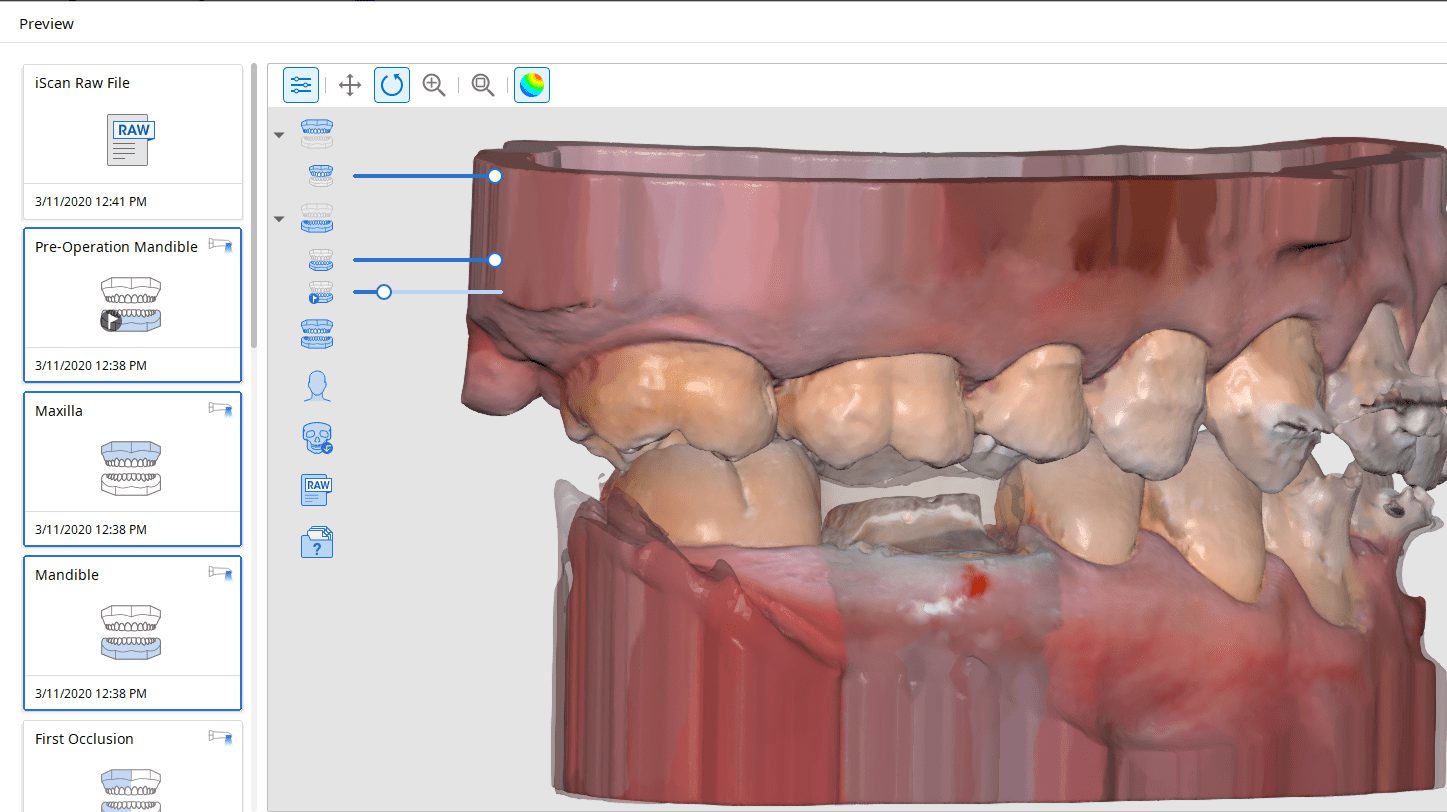

Imaging a deep margin with the Medit i500

In this clinical video we demonstrate how to scan a molar preparation for the replacement of a crown with recurrent decay and open margins. The molar was root canal treated and the tissue was inflamed. the preparation was imaged and a temporary was fabricated to allow the tissue to heal properly.

The main point of this video is to show how to capture the contacts of the adjacent teeth and the deep marings